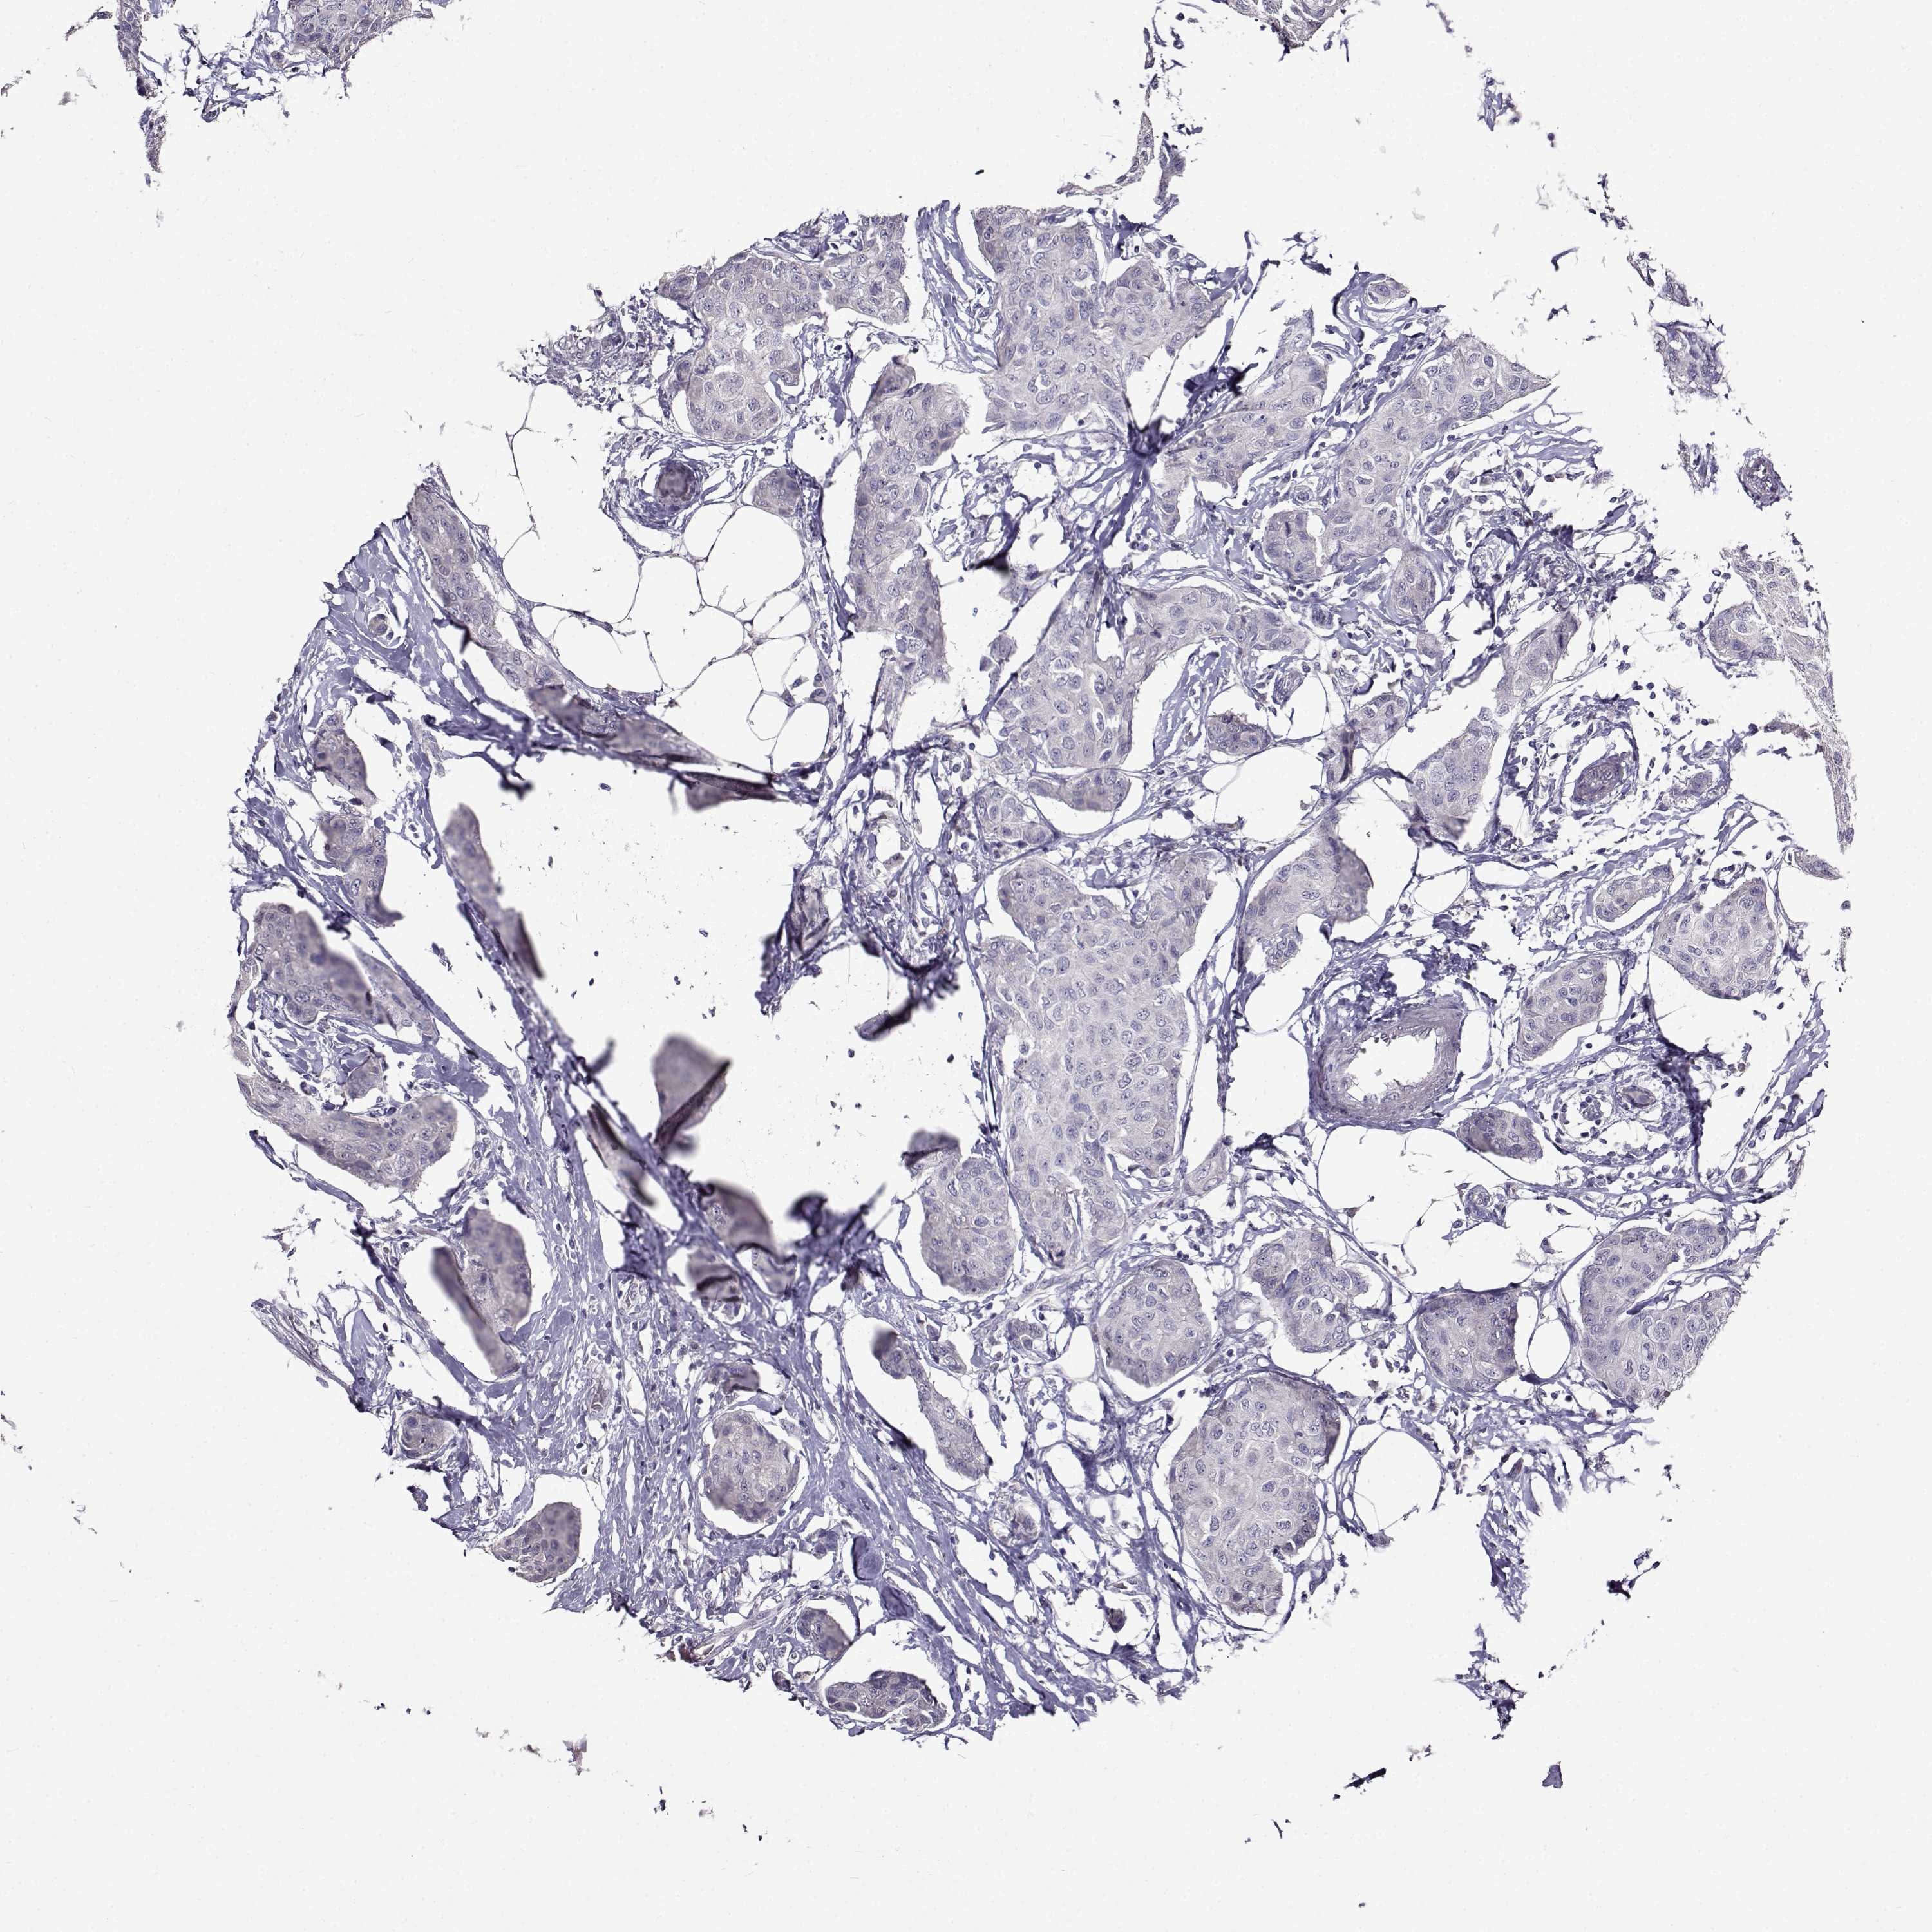

CANCER BREAST CANCER Show tissue menu

BRCA TCGA BRCA VALIDATION PROTEIN EXPRESSION